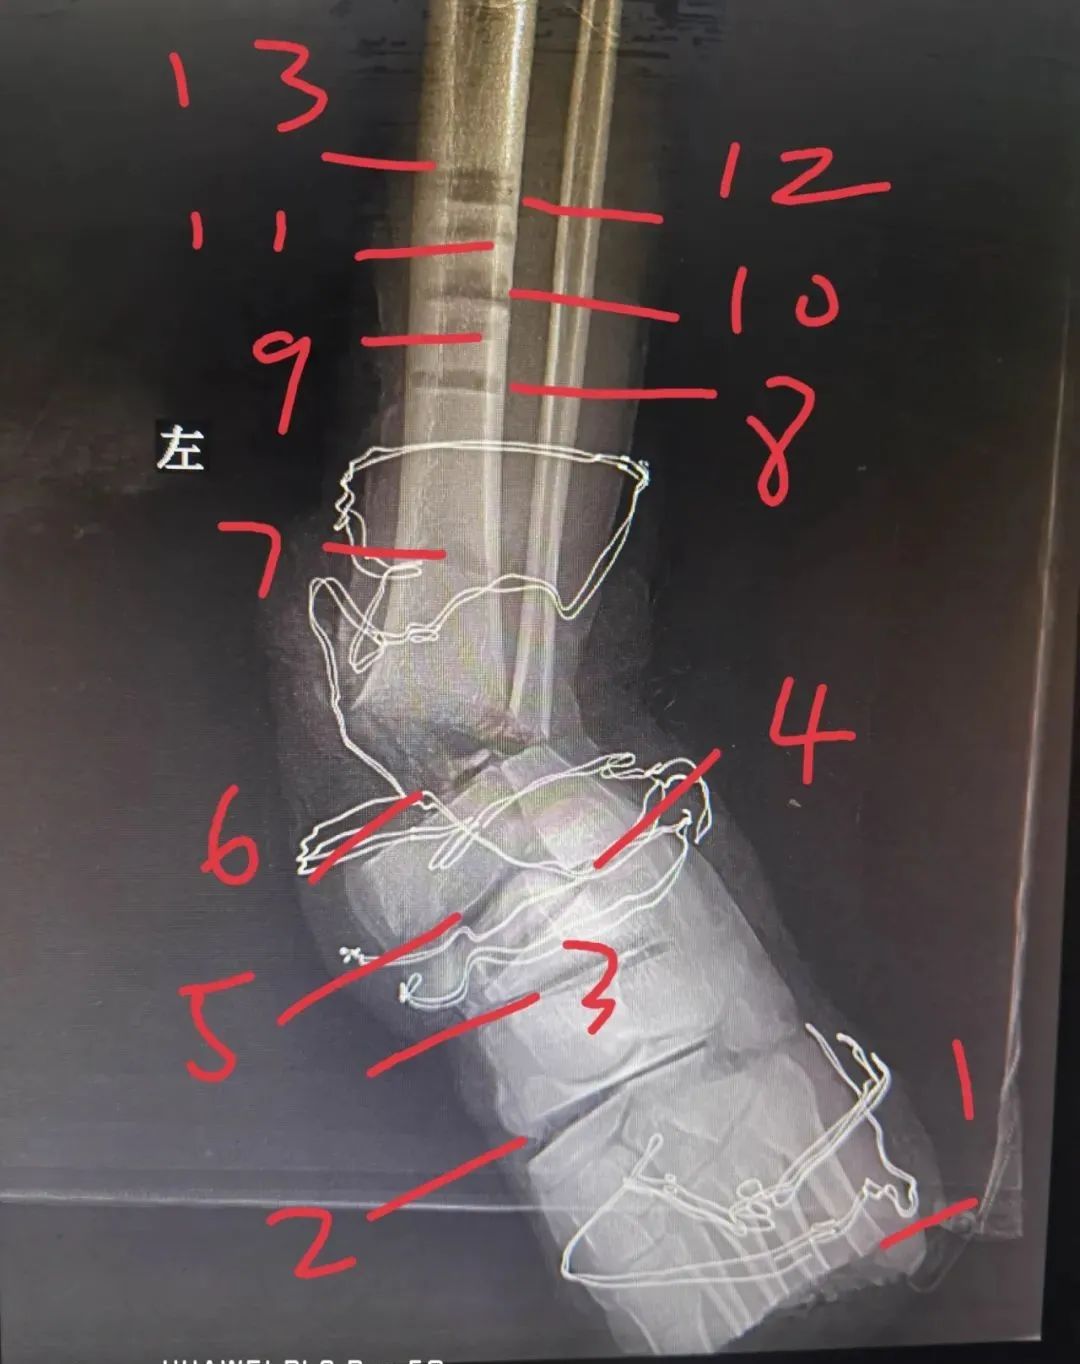

X 线示如下:

二、左小腿切割 13 刀

3、总计 13 刀,平面如下图